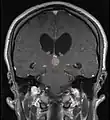

Frequently, paralysis of upward gaze along with several ocular findings such as convergence retraction nystagmus and eyelid retraction also known as Collier's sign and Light Near Dissociation (pupil accommodates but doesn't react to light) are known collectively as Parinaud's syndrome[1] or Dorsal Mid-brain syndrome, are the only physical symptoms seen. This is caused by the compression of the vertical gaze center in the midbrain tectum at the level of the superior colliculus and cranial nerve III. Work-up usually includes Neuro-imaging as seen on the right.